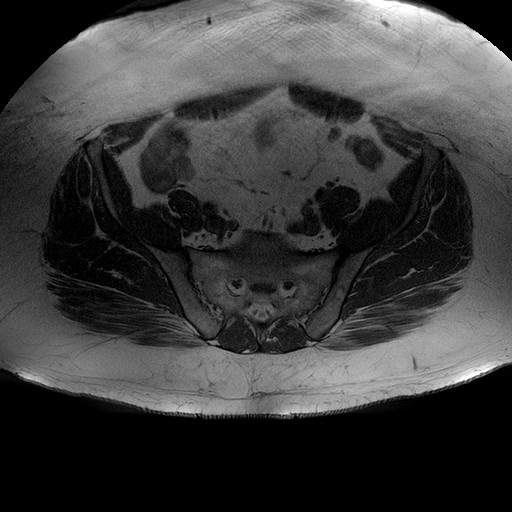

Esami: RMN BACINO

T1W_TSE

Evidenti e simmetriche alterazioni osteofitosiche in regione coxo femorale con riduzione delle rime articolari. Degenerazione completa del cercine glenoideo. Non attuali segni di versamento articolare. Non segni di edema osseo che escludono attuale algodistrofia od osteonecrosi. Lieve e simmetrica riduzione del trofismo della muscolatura glutea.